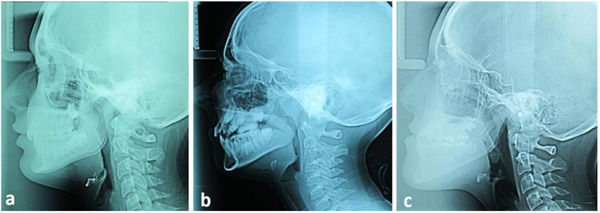

After setting the Frankfurt Horizontal Plane (FHP), 14 measurements were taken at 14 mid-facial landmarks, according to George ([22], Fig. 1): supraglabella (Sg’), glabella (G’), nasion (N’), nasale (Na’), subnasale (Sn), superior labial sulcus (SLS), labrale superius (LS), stomion (Sto), Labrale Inferius (LI), Inferior Labial Sulcus (ILS), Suprapogonion (S Pog’), pogonion (Pog’), gnathion (Gn’), menton (Me’). On each X-ray, the skeletal class was assessed as well: five landmarks were identified, corresponding to the deepest point of the line between the nasal spine and the prosthion (A - subspinale), the deepest point on the line between infradentale and pogonion (B - supramentale), the lowest point of the chin (Menton, Me), the point at the mandibular angle (gonion, Go), and the central point of the sella turcica (S - sella). Angles ANB (subspinale-nasion-supramentale), SNA (sella-nasion-subspinale) and SN-GoMe (angle between the sella-nasion line and the mandibular plane) were measured [18]. Finally, the corrected ANB angle (ANBc) was calculated according to Miralles et al., as follows [23]:

ANBc angles between 0° and 4° were classified Class I, under 0° Class III and over 4° Class II (Fig. 2).